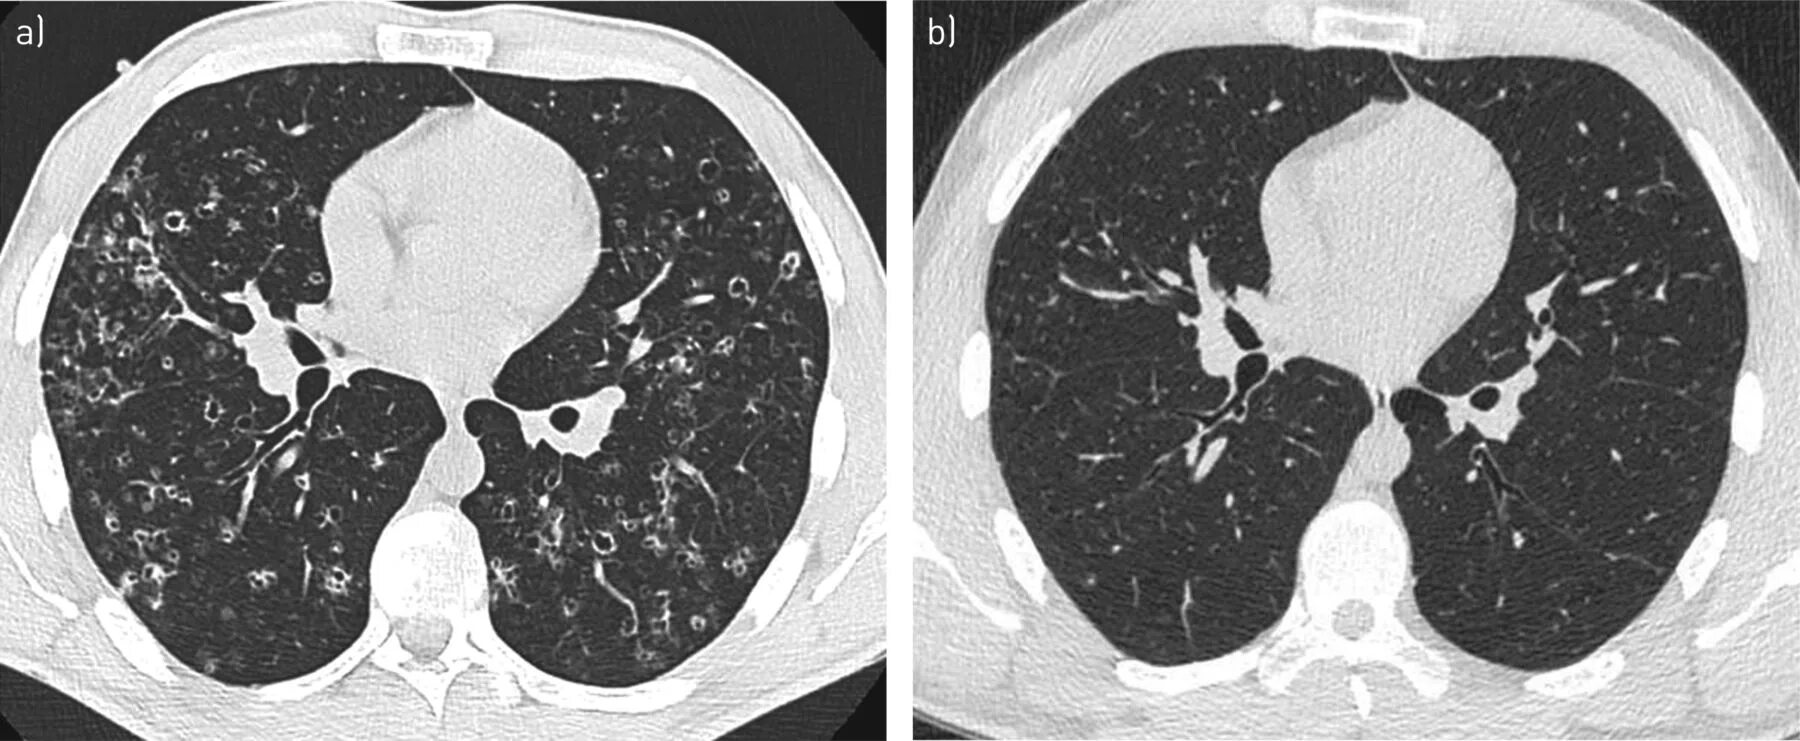

Кт х